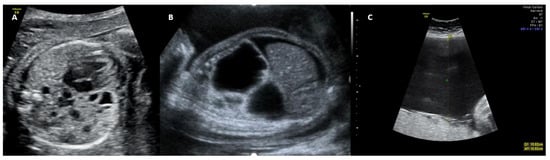

3. Diagnosis and Classification

Early detection is essential for prenatal and postnatal follow-up and is directly related to lesion size, degree of mediastinal deviation, fetal hemodynamics, and associated anomalies [5]. Prenatal diagnosis of CCAM is based on ultrasound findings (Table 1), most commonly detected in the second trimester of pregnancy and classified into three subtypes according to Stocker [5,6] (Table 2 and Figure 1). Although magnetic resonance imaging (MRI) has high sensitivity and specificity for detecting lung lesions, it has not been shown to add diagnostic or prognostic value over ultrasound [4] (Figure 2).

Figure 1. Two-dimensional ultrasonography. Classification congenital adenomatoid cystic malformation. (A) Subtype I, (B) Subtype II, and (C) Subtype III. Source: the authors.